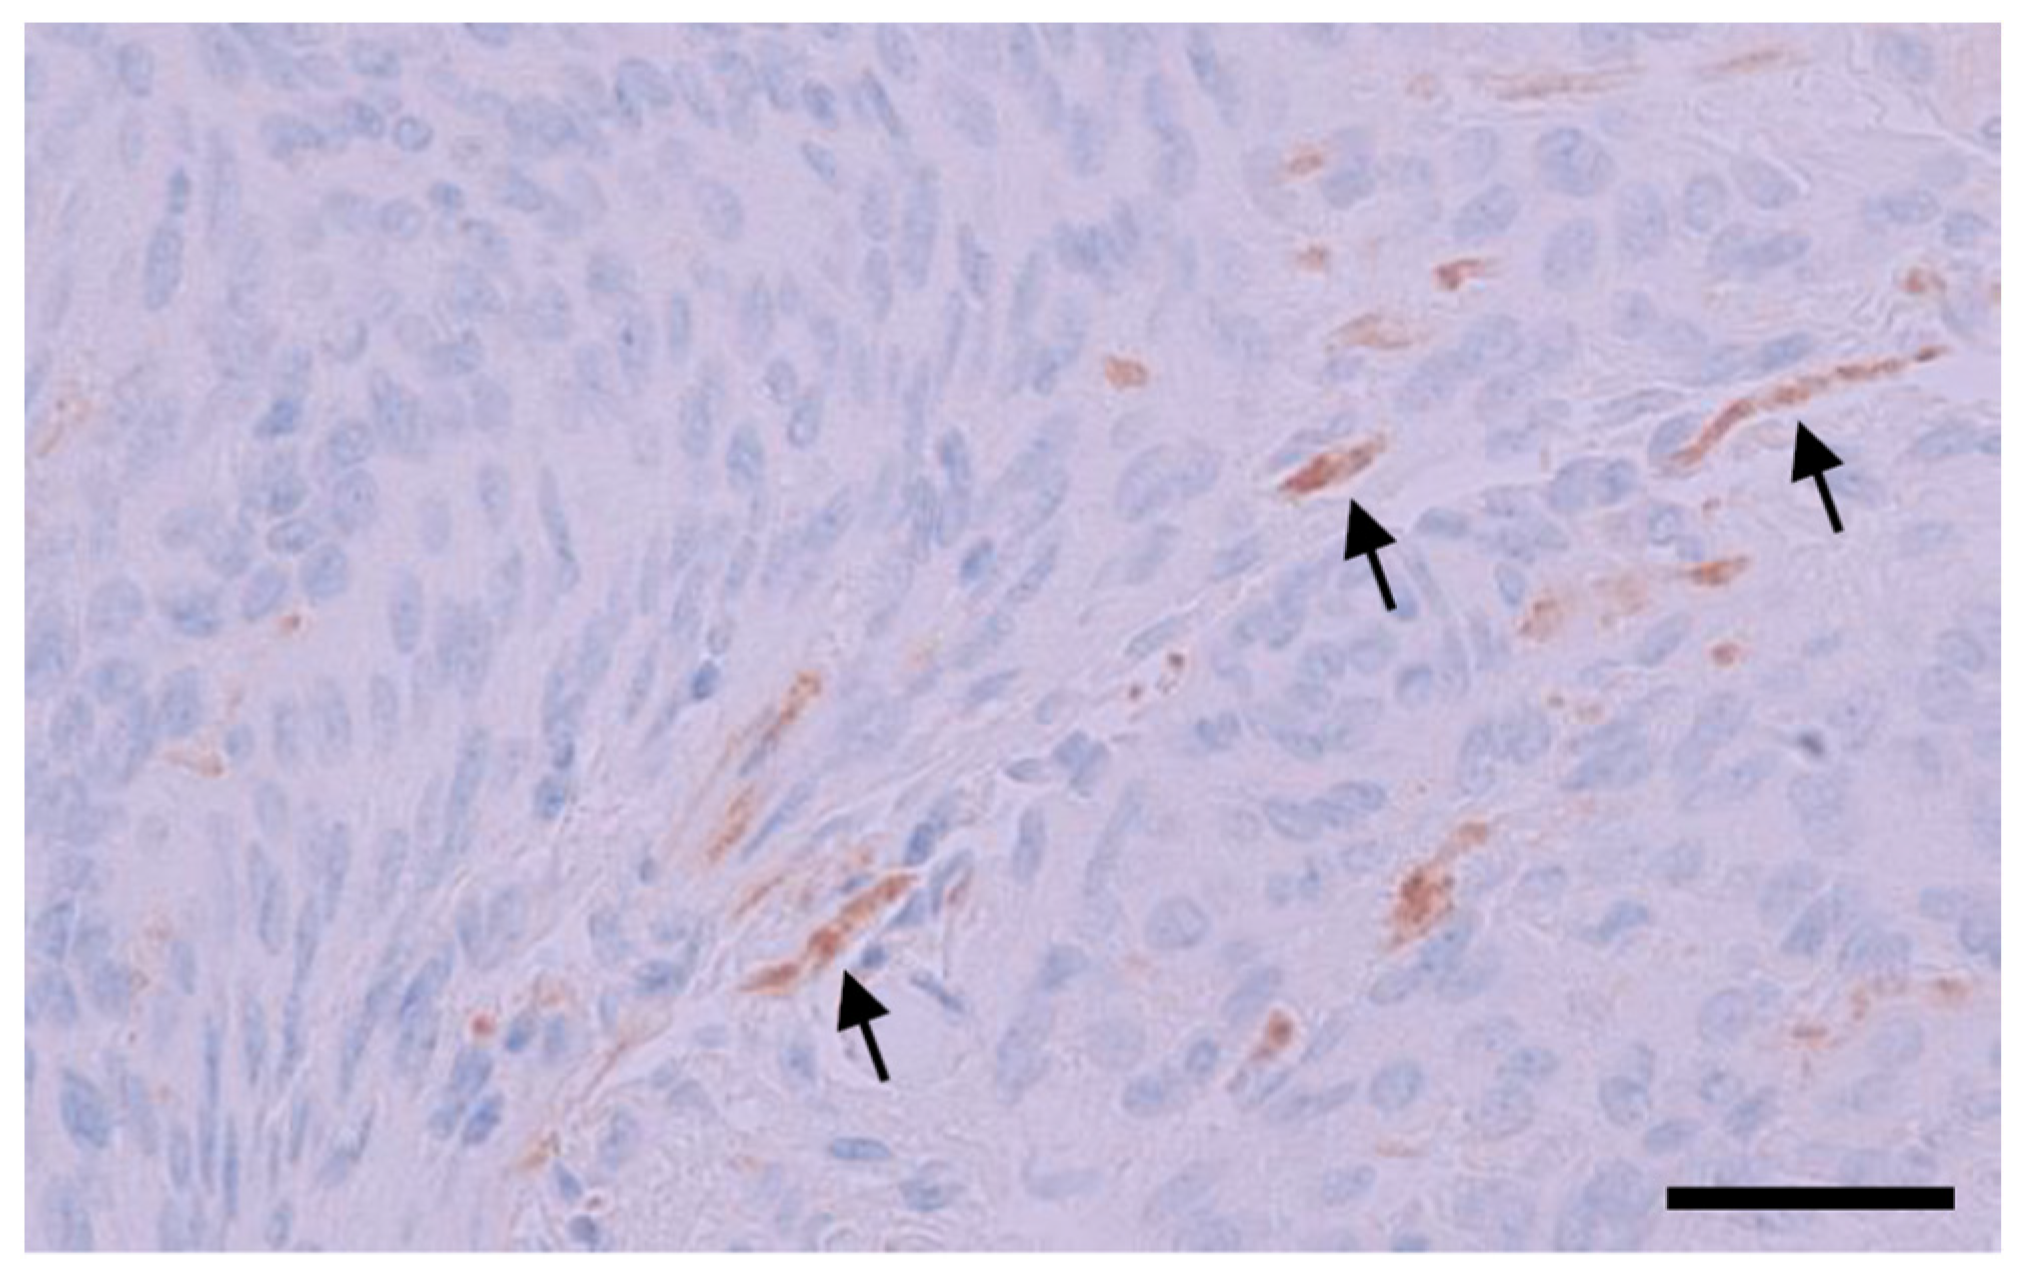

3.4. IHC Binding of MRQ-67 in Diffuse Gliomas